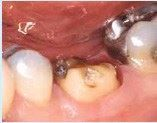

Hvis du har en defekt tand, som det ikke længere er forsvarligt eller muligt at reparere med en fyldning, så det kan holde, er det nødvendigt med en krone. Den vil gøre tanden mere holdbar og skal sikre, at tanden ikke knækker, så du derved risikerer

at miste tanden.

Denne tand kan ikke repareres med en fyldning, en krone er nødvendig.

I andre tilfælde kan en krone være den eneste måde, du kan få et pænt og holdbart resultat på, fx når tanden er misfarvet eller misdannet.